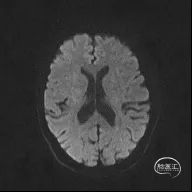

颅脑MR:脑内多发缺血灶、软化灶。